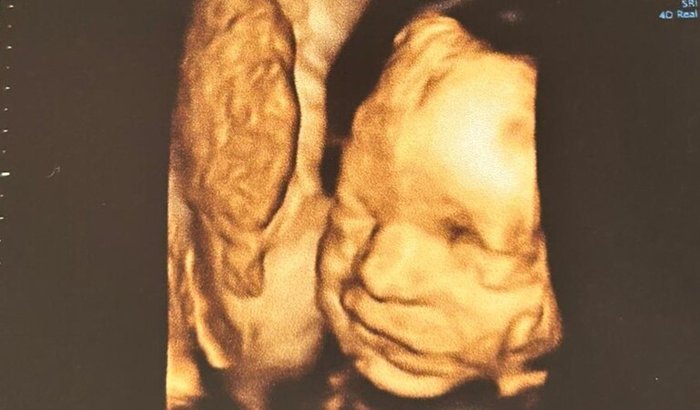

Uma corrente de amor para o pequeno Pedro

Em um exame de rotina, veio a notícia inesperada: o Pedro tem estenose aórtica crítica, e precisaria de uma cirurgia cardíaca urgente, ainda na barriga da mamãe (intrauterina), o primeiro passo para seu coraçãozinho se desenvolver melhor até seu nascimento. A cirurgia, realizada com sucesso, foi uma verdadeira bênção, mas o plano de saúde não cobriu o procedimento.